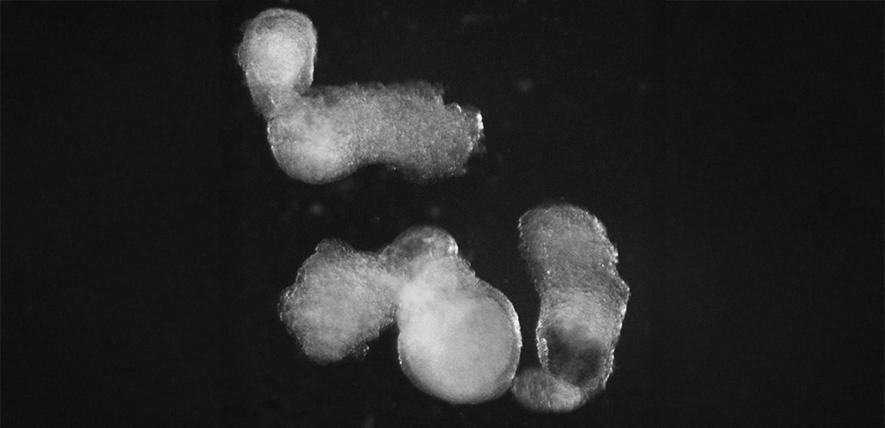

The embryo-like structures, which the scientists have named ‘hematoids’, are self-organising and start producing blood after around two weeks of development in the lab – mimicking the development process in human embryos.

The team observed the emergence of the three-dimensional hematoids under a microscope in the lab. By the second day, these had self-organised into three germ layers – called the ectoderm, mesoderm, and endoderm – the foundations of the human body plan that are crucial for shaping every organ and tissue, including blood.

By day thirteen, the team saw red patches of blood appearing in the hematoids. They also developed a method which demonstrated that blood stem cells in hematoids can differentiate into various blood cell types, including specialised immune cells, such as T-cells.